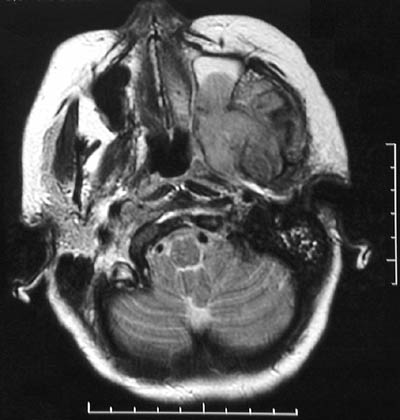

These axial MRI scans of the head of an adult, T2 weighted above and T1 weighted below, demonstrate a large infiltrative mass arising in the left maxillary-pterygoid region. This mass proved to be a

rhabdomyosarcoma

.